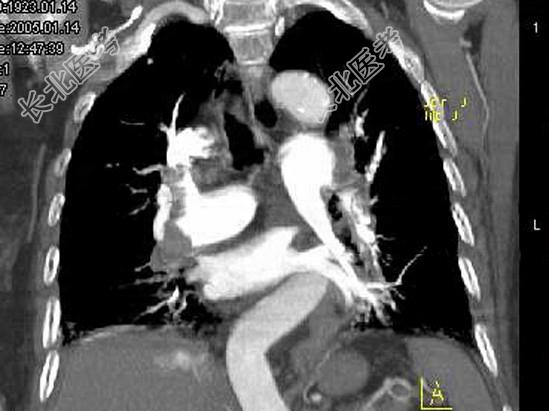

- 单项选择题82岁,女性, 突发右侧胸痛,呼吸急促, 行急诊CT检查,如图所示, 请选择最佳答案 ( )

D、肺动脉栓塞